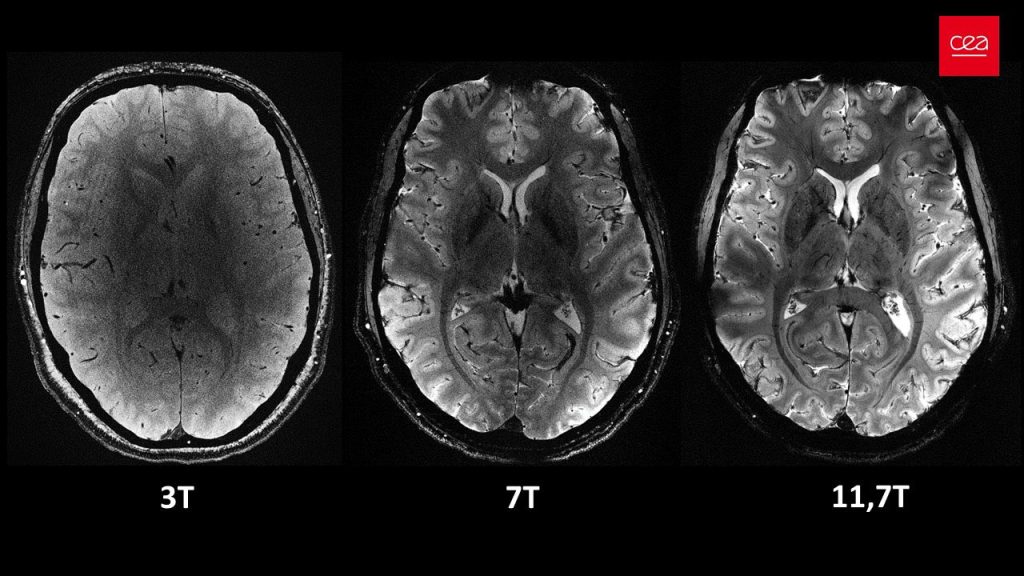

Het apparaat gebruikt sterke magneten en elektromagnetische radiogolven om afbeeldingen te maken. De sterkte van de magneten worden uitgedrukt in tesla. Voor scanners in ziekenhuizen ligt deze tussen de 1,5 en 3 tesla. ‘s Werelds krachtigste MRI-scanner, in Parijs, bereikt echter een sterkte van 11,7 tesla. En dat verschil zie je, zo maakt onderstaande afbeelding – onthuld door de Alternative Energies and Atomic Energy Commission (CEA) – duidelijk.